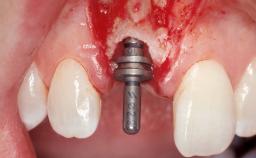

Immediate Flapless Placement of an Implant in a Maxillary Right Lateral Incisor Site

This 43-year-old male patient, a non-smoker, came to our practice because of a fracture of tooth 12 caused by a bicycle accident. Due to the combined para- and infrabony crown and root fracture, tooth extraction, and subsequent implant placement were suggested to the patient as the therapy of choice. The patient had high esthetic expectations with regard to the treatment outcome and asked for an immediate fixed provisional restoration. His individual esthetic risk profile summed up to a medium esthetic risk.

Type of Implants Two-Piece

Placement Protocol Immediate implant placement

Tooth Site Maxillary incisor or canine

Loading Protocol Immediate

Retention Screw-retained Screw-retained